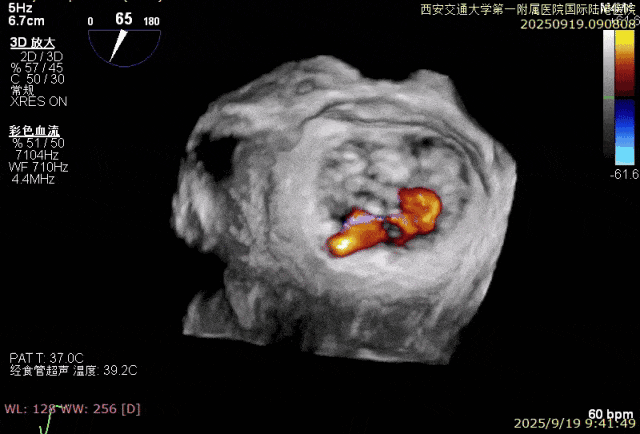

患者男性,69岁,术前TEE评估为FMR患者,因左室功能异常引发二尖瓣重度反流;后叶拴系,反流来源于整个2区,主要集中在2偏1、2偏3。患者瓣口面积约6.2cm²。房间隔可穿刺高度4.5cm。反流束宽度约19mm。AP径36.5mm。

经专家团队评估后决定于2区正中位置先植入一把XTR,植入后评估反流改善情况,如仍有反流,可调整第一把夹子放置于2区偏内,再于第一把夹子外侧植入第二枚夹子,改善对合和反流。

术中在超声引导下完成房间隔穿刺,将第一枚XTR在左房内完成终定位,2偏3区完成植入,夹合效果良好,即刻超声显示轻微反流,完成夹子释放,手术效果良好,手术圆满结束,患者术后6小时即实现床旁活动。